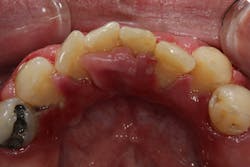

- 10% to 20% of the cases are typically attributed to calcium channel blockers, with nifedipine being the most notable problem (figures 4a and 4b).

Another laser that has been used to treat gingival enlargement and gummy smiles is a 9.3 micron CO2 laser (Solea from Convergent Dental; figure 2a). Unlike other lasers, the Solea laser has the capabilities of removing both soft and hard tissue, precise cutting accuracy due to control of both laser beam power and size, and the ability to cauterize inflamed tissue (figures 4c and 4d). Conventional instrumentation—such as blades, knives, and high-speed burs—can often lead to bleeding after surgical removal when the tissue is inflamed. With this type of CO2 laser, sutures and/or surgical dressing are often not needed.